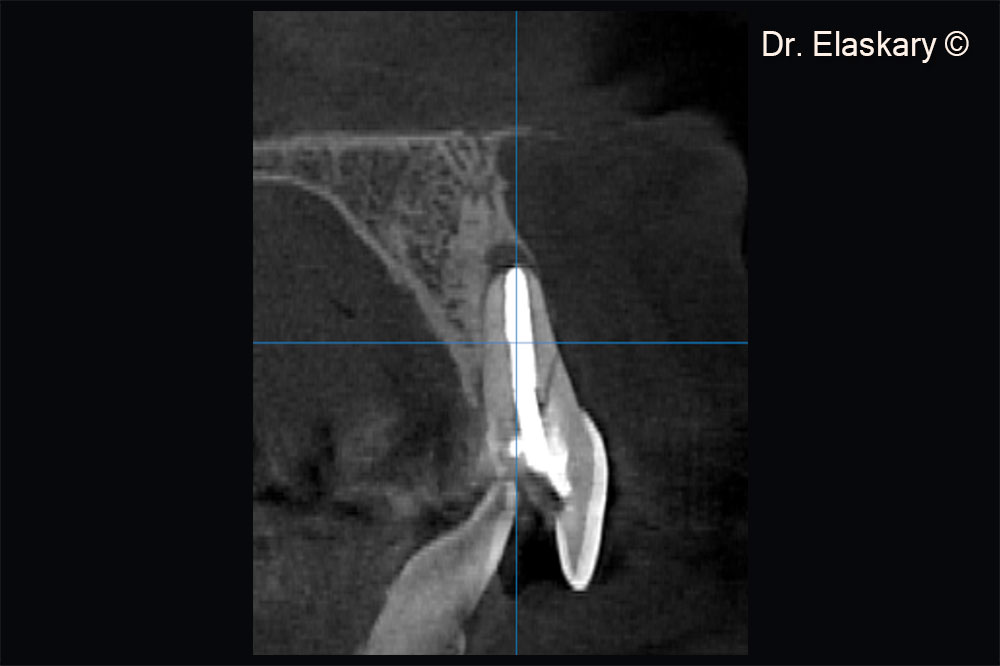

CBCT scan showing a sagittal section of broken central incisor , with lost labial plate of bone